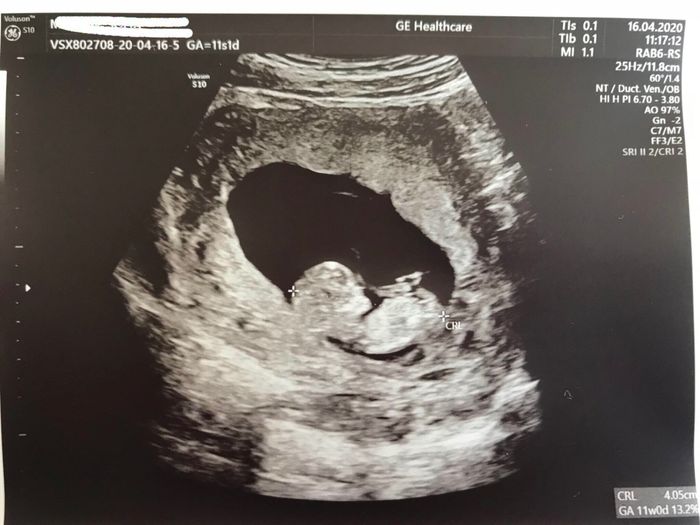

Non ti scoraggiare, queste sono le mie...5 settimane, 8settimane e 11 settimane, crescono dal giorno alla notte, a 8 era 1,6 cm e a 11 già 4,5 cm😍

Eco 5+5 1

Eco 5+5 2

Eco 5+5 3